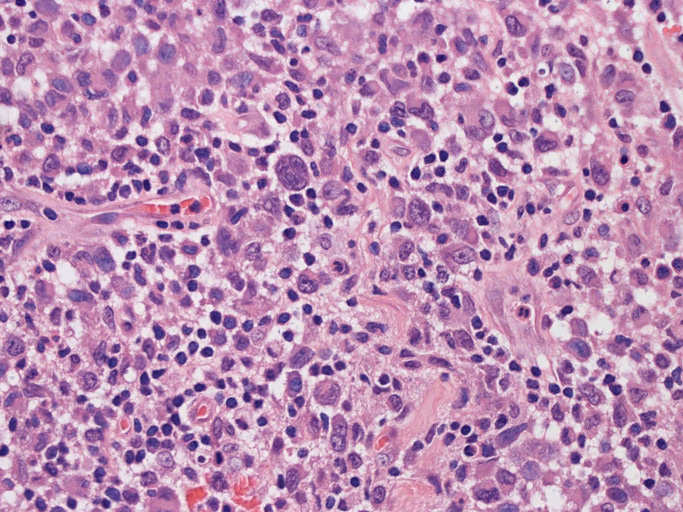

皮膚に異型細胞の浸潤がみられる。異型細胞は表皮内に浸潤するほか、表皮真皮境界部, 真皮, 皮下脂肪組織にもびまん, 結節様の浸潤所見を示す。血管周囲に浸潤、集蔟する所見も多く見られる。 増殖浸潤細胞の核には類円形や腎臓形, またはへこみ, 切れ込み, 溝などを有する多型な核が認められる。クロマチンは粗でvesicularな核が多い。核小体の明らかな核もある。好エオジン性の核内封入体様構造も少数に見られた。mitosisは容易に認められる。hyperchromaticな多型核, bizzarreな細胞が高頻度に認められ異型度は高いと考えられる。細胞質は境界不明瞭, 淡明または泡沫様の 好エオジン性胞体である。

免疫染色 浸潤細胞はCD1a+, S100+, Langerin+, HLA-DR+, CD4+, CD45+, CD68+. MIB-1 index:24.4%

Speaker's Pathological Diagnosis: Langerhans cell sarcoma, skin, rt. knee, biopsy